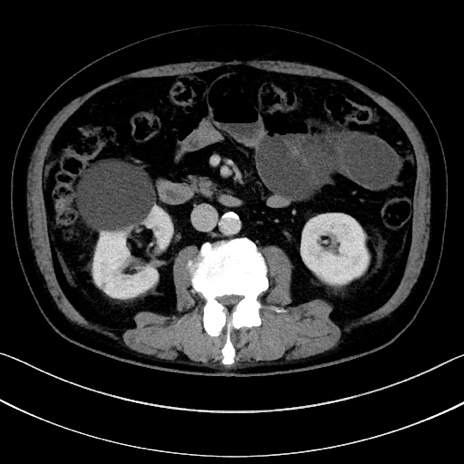

症例15(横断像)

【症例】70歳代男性

【主訴】腹痛

【現病歴】今朝から腹痛あり。全体的に痛い。特に左上の方。排ガスが今日はない。冷や汗が出る。

【既往歴】直腸癌術後

【身体所見】左側腹部〜上腹部に圧痛あり。腹膜刺激症状明らかなではない。軽度反跳痛。左下腹部に術後瘢痕あり。

【データ】WBC 7700、CRP 0.02